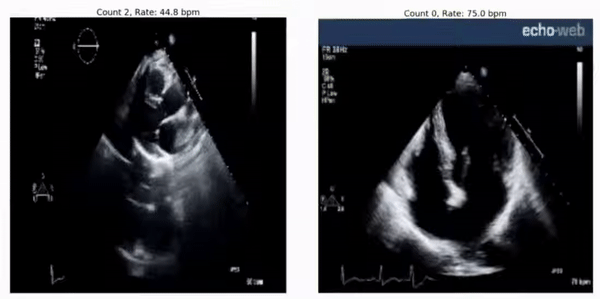

RepNet 可用于评估来自超声心动图的心跳节律,即便其在训练期间并未见过这样的视频:

预测得到的心跳速率:45bpm(左边)和 75bpm(右边)真实的心跳速率分别为 46-50 bpm 和 78-79 bpm。RepNet 对来自不同设备的数据的心跳速率预测非常接近该设备实际测得的心跳速率。